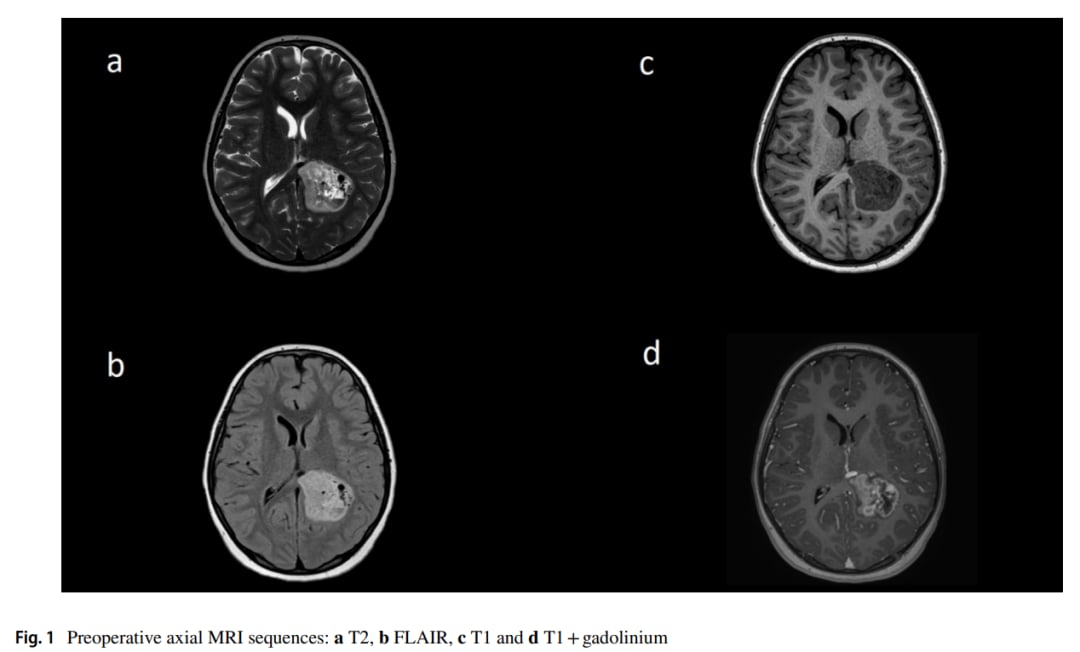

▲图2 术前动脉晚期DSA结果

本文首次详细报道了一例大型AVM与分子定义的乳头状胶质神经元肿瘤(PGNT)在空间和时间上共存的病例。一名10岁女童因持续头痛和恶心就诊,MRI检查显示左侧顶叶存在病变,并伴有明显的血管异常。数字减影血管造影(DSA)进一步证实了高流量动静脉畸形的存在。在遵循AVM手术原则成功切除病变后,组织病理学和基因测序结果令人瞩目。

病理分析显示,肿瘤由相对单一形态的小上皮样细胞组成,具有血管周围假菊形团结构。更关键的是,全基因组测序检测到了SLC44A1::PRKCA融合,这正是乳头状胶质神经元肿瘤的特征性分子改变。这一发现不仅确诊了肿瘤类型,也为理解其与AVM的共存提供了分子层面的线索。